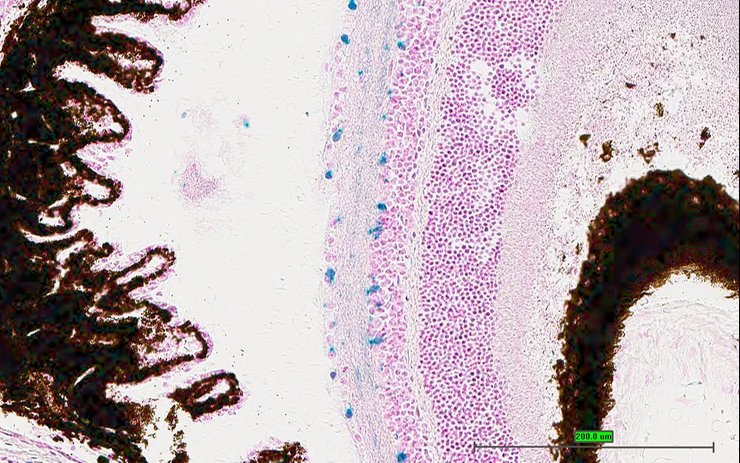

TS28: eye Present UC Davis_1868090

Specimen UC Davis_1868091: postnatal adult; Cnr1tm1.1(KOMP)Vlcg/Cnr1+ (more )